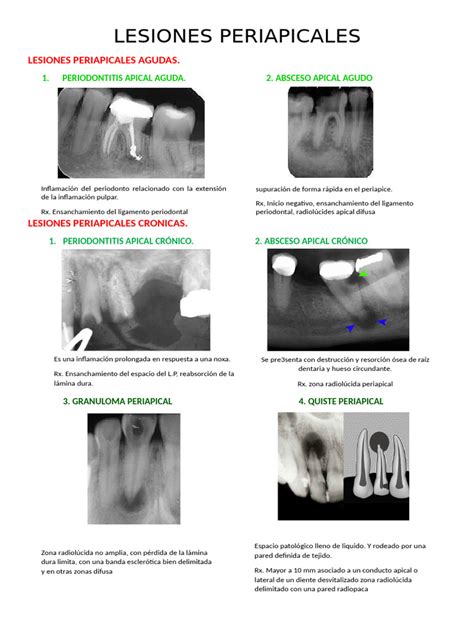

Enfermedad Periapical

Cuando la infección se extiende a los ápices dentarios, se produce la llamada enfermedad periapical. Este término engloba un espectro de enfermedades que ocurren en torno al ápex del diente, incluyendo el absceso periapical, el granuloma periapical y el quiste periapical.

La osteólisis derivada de los cambios inflamatorios se manifiesta inicialmente en la TCMD como un ensanchamiento del espacio periapical, a expensas de un fino halo radiolúcido que rodea la raíz y el ápex.

Los abscesos periapicales se producen ante infecciones que el sistema inmunitario no consigue controlar. Suelen acompañarse de fiebre, dolor y signos inflamatorios locales. Radiológicamente se manifiestan como lesiones líticas periapicales que presentan signos de actividad en forma de bordes mal definidos y cambios de osteomielitis aguda asociada.

Ante una infección latente localmente persistente, con el tiempo pueden desarrollarse granulomas periapicales (tejido de granulación encapsulado) o alternativamente quistes periapicales (por proliferación de células epiteliales secretoras). El quiste suele presentar mayor tamaño, crecimiento con el tiempo y bordes mejor definidos que el granuloma, aunque radiológicamente pueden ser indistinguibles.